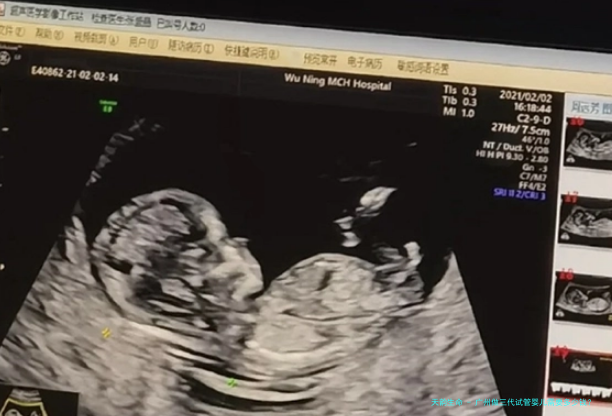

胚胎检查结果出来,女身体吻合移植先决条件,等候下个月经周期移植就可以了。正常情况下,只需要十分钟左右就能够做到胚胎移植手术,手术之后在医院观察2-四个小时,没出现不适反应就可以回家了。胚胎移植后7天,便可以到医院采血查看三代试管婴儿妊娠结果,要是妊娠成功,应在妊娠后第一四日做B超检查,以认定胎儿数目和植入位子。